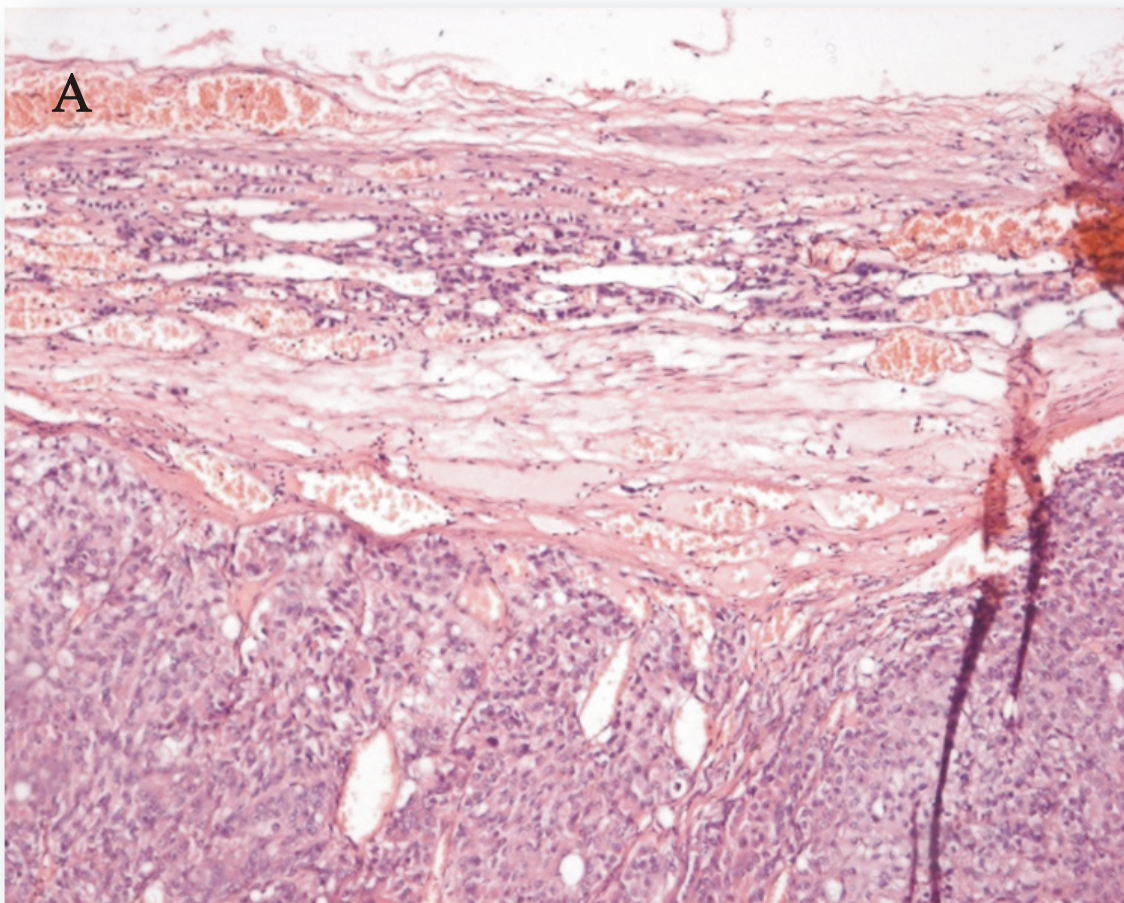

Рис. 1. Клиническое наблюдение № 1. Пациентка К. – адренокортикальный рак, при микроскопии визуализируется капсульная инвазия (окрашивание гематоксилином и эозином, Х100)